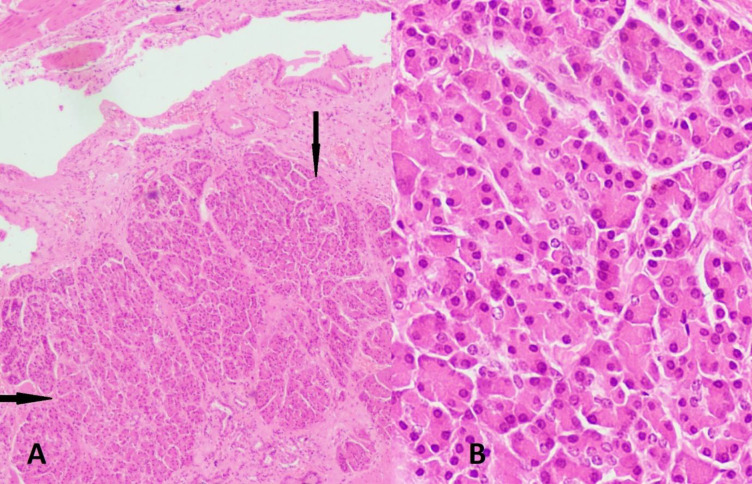

Case presentation: We hereby report a case of incidental discovery of ectopic pancreatic tissue in the excised gallbladder from a 27-year-old female who presented with nausea, vomiting, and abdominal pain intermittently. The gallbladder lumen was filled with biliary sludge containing a single gallstone. Histopathology revealed chronic cholecystitis along with a tiny focus of ectopic pancreatic tissue comprising only pancreatic acini.